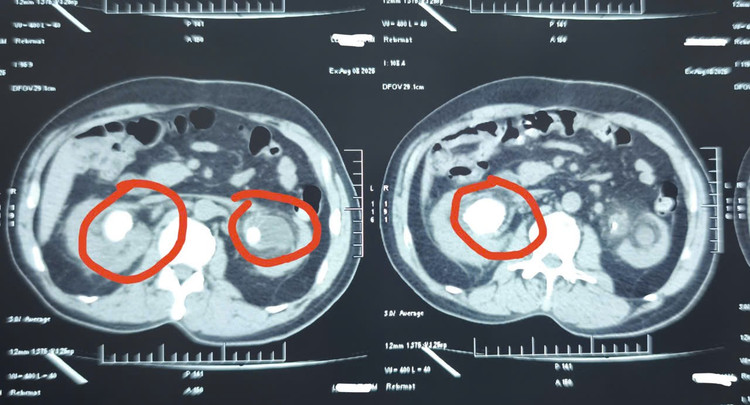

“Qua thăm khám, chúng tôi không thể rút sonde JJ bằng biện pháp thông thường. Do thời gian lưu sonde quá lâu, bệnh nhân được chỉ định chụp CT. Kết quả cho thấy sỏi bám vòng quanh sonde JJ chiếm gần như hết diện tích đài bể thận 2 bên. Thận phải có viên sỏi lớn 34x29mm, thận trái 20x13mm kèm nhiều viên nhỏ rải rác. Sỏi ở trên thận gây ứ nước thận độ 3.

song-4.jpg

Hình ảnh sỏi thận trên phim chụp - Ảnh BVCC

Đặc biệt, chỉ số Kali trong máu của bệnh nhân lên đến 6.9 mmol/L (bình thường Kali máu từ 3.5 mmol/L -5.0 mmol/L), có nguy cơ ngừng tim bất cứ lúc nào. Vì vậy, bệnh nhân được đưa đi lọc máu cấp cứu ngay lập tức”, bác sĩ Trần Duy Hiến, Khoa Ngoại Tổng hợp, Tiết niệu và nam học cho biết.